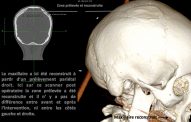

Les photos qui illustrent le texte ont pour unique objectif de vous aider à mieux comprendre les techniques utilisées. Elles correspondent chacune à une réalité qui ne peut être transposée car chaque situation clinique est différente et unique.

L’intervention chirurgicale consiste en une reconstruction osseuse du maxillaire ou de la mandibule avant la mise en place des implants dentaires par votre chirurgien.